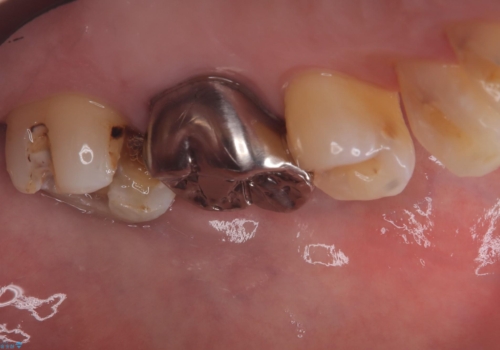

- 主訴:フロスを通したら、詰め物が取れた。適合の良いものを入れたい。

保険適用のメタルインレーが脱離しており、適合重視・咬合力が強いことからゴールドインレーでのやり替えとなりました。

フロスを通しインレーが脱離したことから、インレーと歯質との境に段差(適合不良)があった可能性があり、適合の良さや咬合力による補綴物の破折リスクを考慮し、ゴールドインレーでのやり替えとなりました。